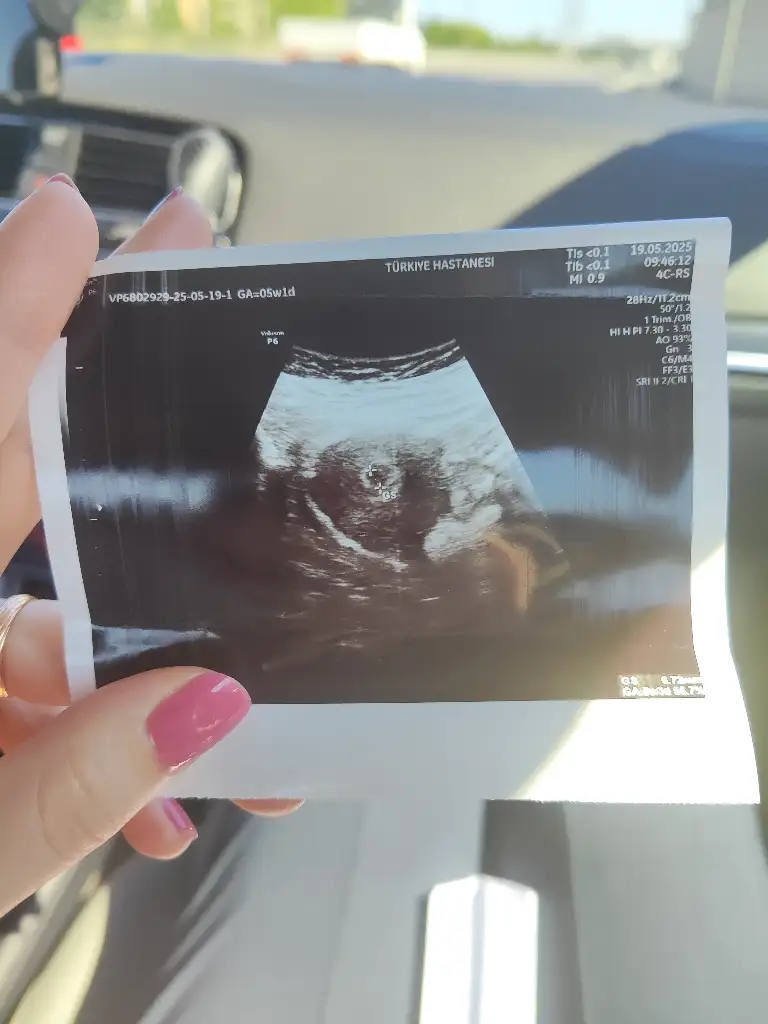

Sabah gittiiik ultrasona girdik, kese göründü keseye göre 5+1 dedi doktor. Sağlıklı bir kese ve rahmin üst kısmında güzel yere tutunmuş tam istediğimiz gibi dedi. İlk fotomuzu de ekleyeyim

AdChoicesHaftaya salı -carsamba falan gel kalp atışı da bakalım dedi.